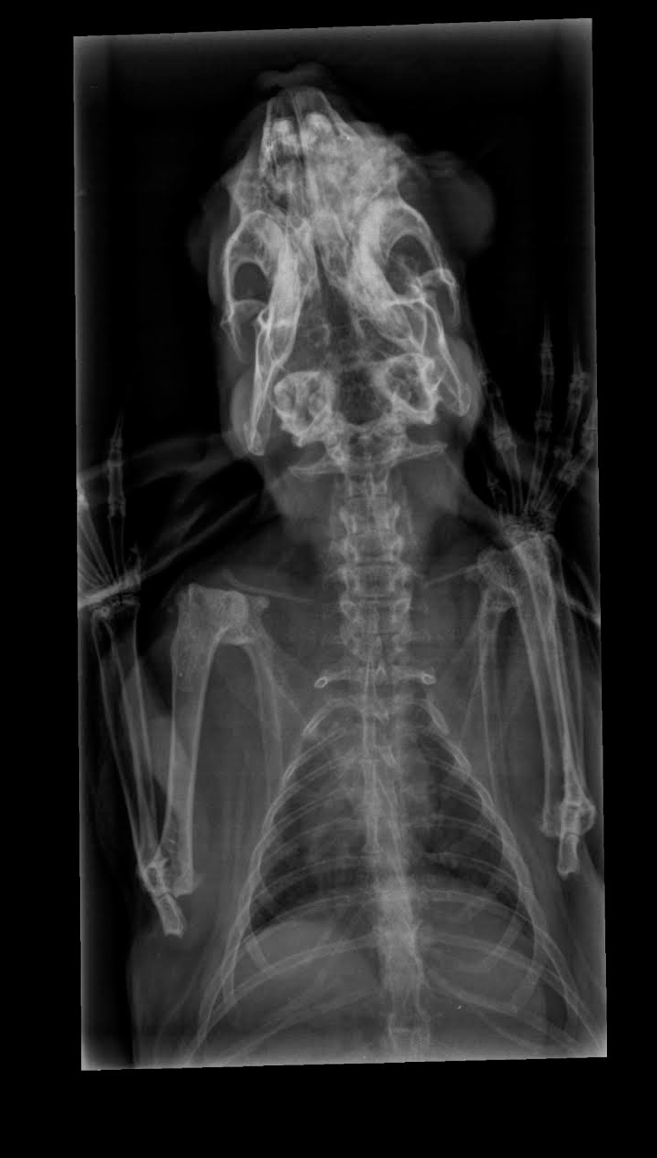

Röntgenfoto’s bij de dierenarts

In januari gingen we ook – zoals ik het vorige stuk al schreef – opnieuw naar de dierenarts met Juve. We hadden inmiddels al een paar maanden van alles geprobeerd, en het mocht allemaal net niet baten. Onze dierenarts had voorgesteld om toch een röntgenfoto te maken, omdat ze bang waren dat er misschien iets mis was met zijn gebit. Dit vonden we onwijs spannend, want hierbij was een roesje nodig – wat bij konijnen, al helemaal op latere leeftijd, erg riskant kan zijn. Ze stelden ons gerust, en we lieten hem een dagje achter bij de praktijk.

Het antwoord dat uit deze röntgenfoto’s kwam, was helaas anders dan verwacht. Juve heeft een tumor op zijn neusbeen. Dit betekent dat de dierenarts ook niets meer kan doen. Hij is daarnaast een bejaard konijn die al een langere tijd in zijn reservetijd zit. We vertroetelen hem zolang hij nog bij ons is. Dat is alles wat we nu kunnen doen.